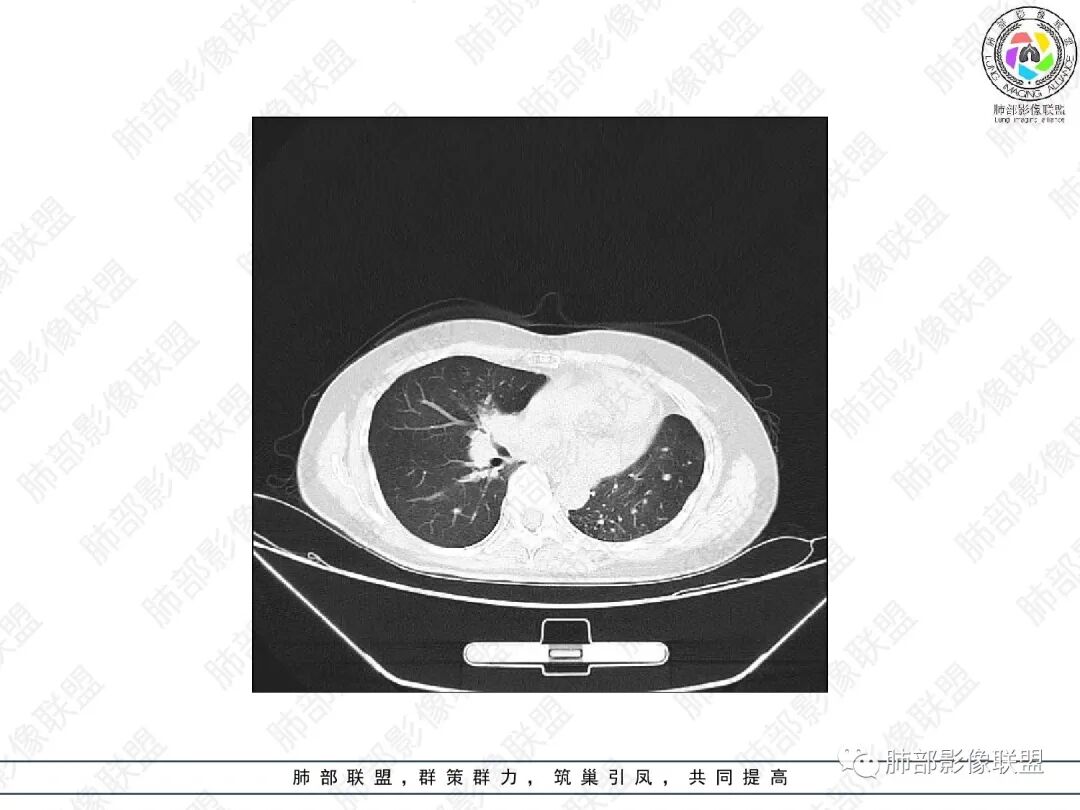

1.中年女性,主因“咳嗽、咳痰半年余”入院,既往史:8年前因左肺病在外院变行左肺叶切除术,诉术后抗结核治疗1年,具体病理等不详。实验室IGE显著增高。

2.胸部CT:右肺上叶及中叶不规则块状影,沿支气管走行方向指套样影,支气阻塞湖嵌塞,腔内可见高密度影。灶周可见磨玻璃,外围见结节影及树芽征。左肺体积缩小,见不规则条索影、胸膜增厚,纵隔牵拉左移。

3.综合分析:结合患者病史及胸部CT主要鉴别ABPA(右肺上叶不规则块影,指套样顺延支气管方向,抗结核治疗1年,肺部病灶仍明显)及继发性肺结核TB(右肺上叶不规则肿块,其可见高密影,边缘模糊,周围卫星灶、树芽征,沿支气管爬行)。

完善气管镜及病理、检验结果(IgE显著增高)等支持ABPA诊断。且给予激素及伊曲康唑治疗后复查胸部CT提示病灶较前吸收,所以诊断明确。